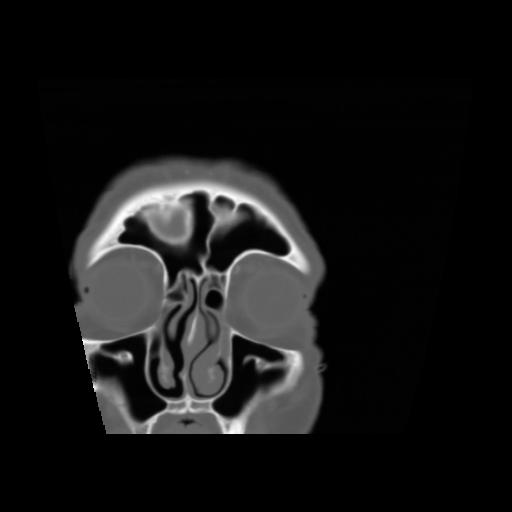

5 CEREBRO,,Coronal,3.000,CEREBRO,Coronal,